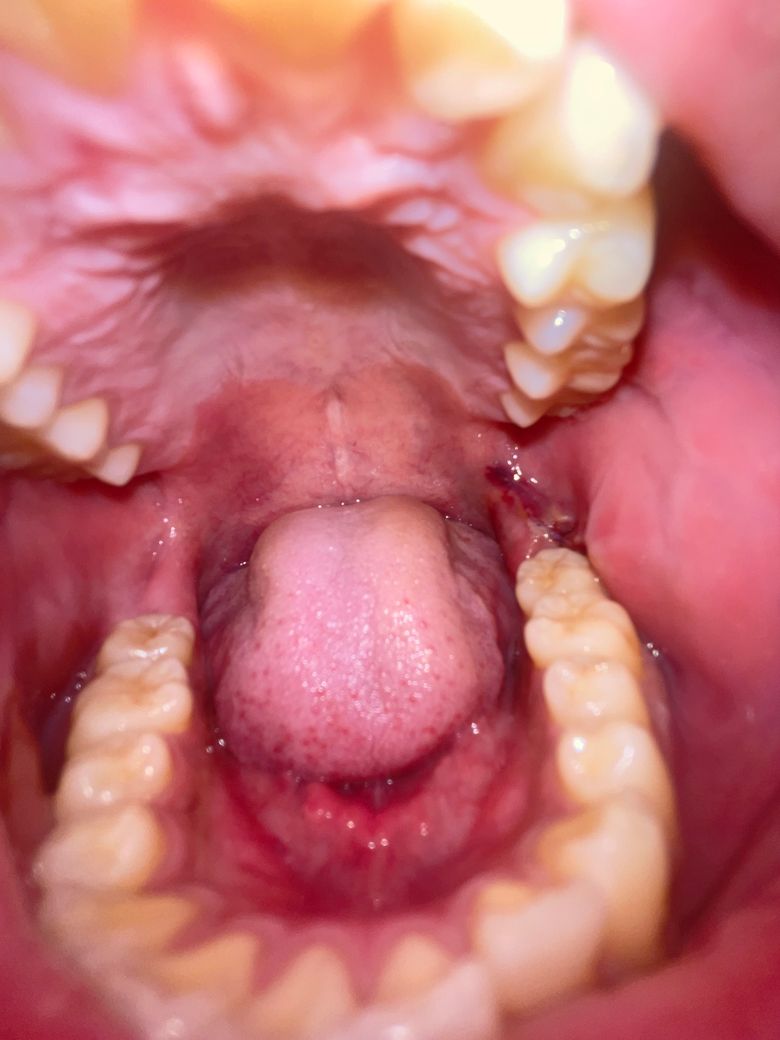

매복 사랑니 발치 3일차입니다 잘 회복되고 있나요?

매복 사랑니를 발치한지 3일차 되는 날입니다.

그런데 오늘 일어나보니 상처부위가 벌어진 것 같아서 여쭤봅니다.

잘회복되고 있는지요 아니면 혹시 드라이소켓인가요?

• 1번 째 사진

현재 사진으로는 정확한 판단이 어렵습니다. 하지만 특별히 통증이나 불편감이 크지 않다면 정상적인 회복 과정일 가능성이 높습니다. 해당 부위의 회복이 지연되거나 문제가 생긴다면 참을 수 없을 정도의 극심한 통증이 나타납니다.

드라이 소켓은 감염의 일종으로 냄새와 통증이 심합니다. 사진상으로 보면 크게 문제가 잇어 보이진 않습니다.

현재 사진상에서는 발치부위에 크게 문제가 있어보이지 않습니다. 가능한 염증이 덧나지 않도록 음주와 흡연은 발치 후 7일간은 피하길 권합니다.

사진상으로는 특별히 문제가 되는 것은 보이지 않습니다. 극심한 통증이 있으면 치과 가보시면 됩니다.

드라이소켓은 보통 극심한 통증과 악취가 동반되는 치유부전입니다

아직 날짜상으로 잇몸치유는 초기단계이며 구멍은 최소 1~2주는 되어야 메워집니다

사진으로만 봤을 경우에는 잘 아물고 있는것으로 보입니다.

해당부위를 자극하지 마시고 사랑니를 발치한 부위는 보통 2주정도 걸립니다.